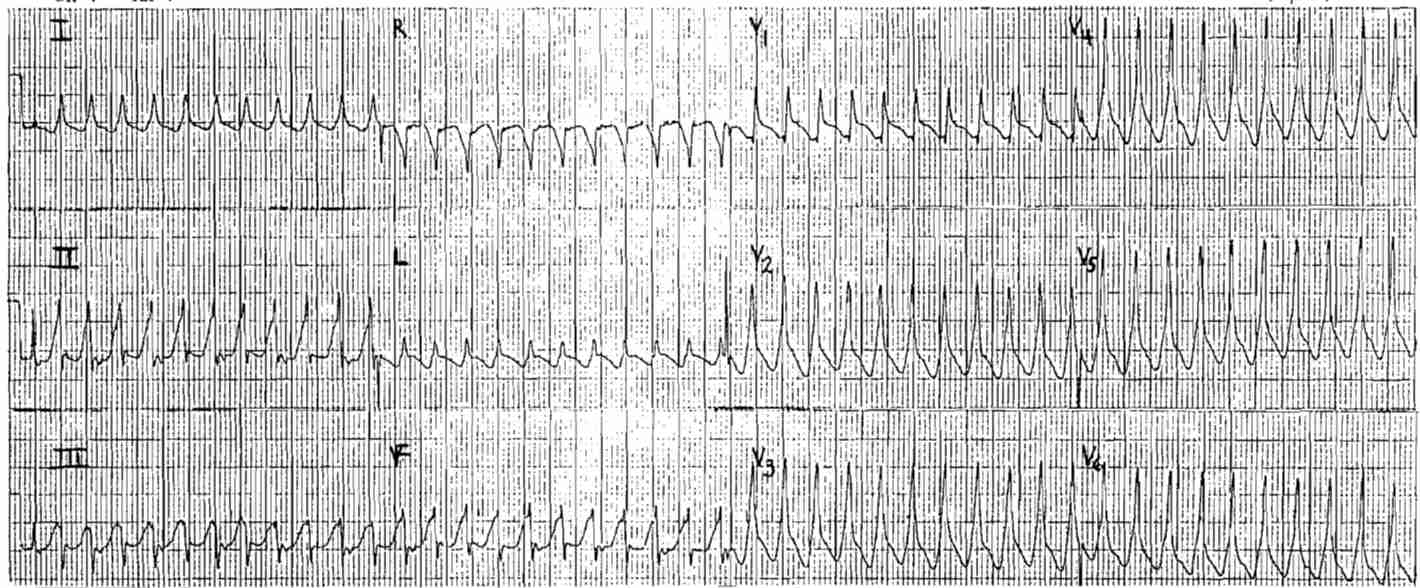

Does this Wide complex tachycardia represents Ventricular Tachycardia or Supraventricular Tachycardia with abberancy?

- The QRS axis is normal – this could be VT or SVT

- The QRS is wide, over 0.14s

- The QRS complexes are upright in all the precordial leads (positive concordant pattern) – this favors VT

- The morphology is not typical for RBBB – this would support VT

- Absence of an RS pattern strongly favors VT

- The most compelling point is provided in the ladder diagram bellow. There are retrograde P waves following every other QRS complex. This represents ventriculo-atrial conduction (VA association) and makes VT a virtual certainty.

So the diagnosis is Ventricular Tachycardia.